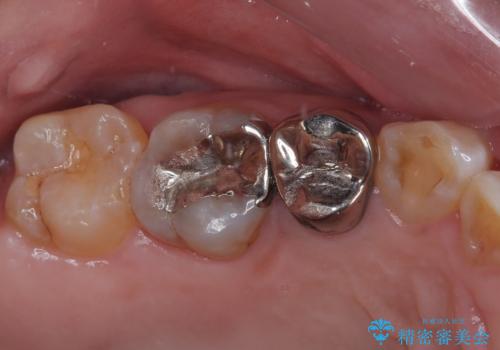

- 笑うときに目立つ銀歯を白くしたいとのことで来院された患者様です。

奥歯ではありますが、以前抜歯矯正をされているので前の方へ移動しており、非常に目立っていました。

仮歯に替えた上で、速やかにオールセラミッククラウンにて補綴治療を行うこととしました。